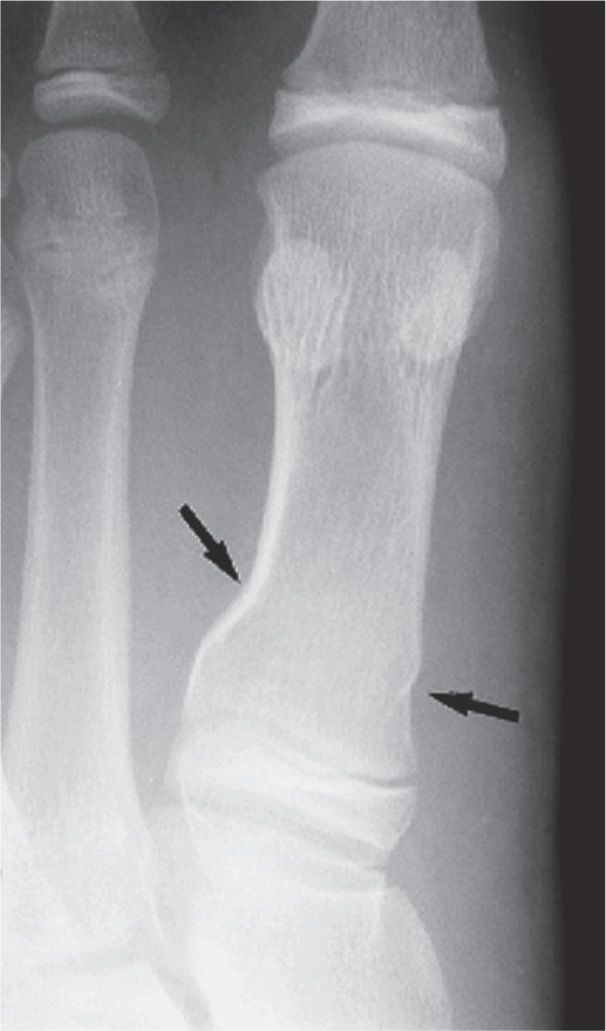

15 Fractures and Related Conditions Fundamentals Musculoskeletal Key

What Is A Buckle Fracture In Leg . They happen when one side of the bone buckles, or bends, but doesn’t break all the way through. Buckle fractures are compression fractures and are very common in children. It does not affect the other side. Torus fractures (also known as buckle fractures) are partial breaks of the long bones (large bones in the arms and legs) in. A buckle fracture is an incomplete fracture where one side of the bone buckles or bends on itself; Your child has been diagnosed with a buckle injury. Buckle fractures are incomplete fractures of bones and happen mainly in children. “a buckle fracture describes a condition where one side of a bone bends and buckles on itself even though the other side of the bone is not disrupted,” explains dr. This information leaflet helps to explain what a buckle injury is and how it is treated. Learn about their causes, symptoms, and. A buckle fracture is sometimes referred to as an “incomplete fracture,” because the break is only on one side of the long bone of the arm.